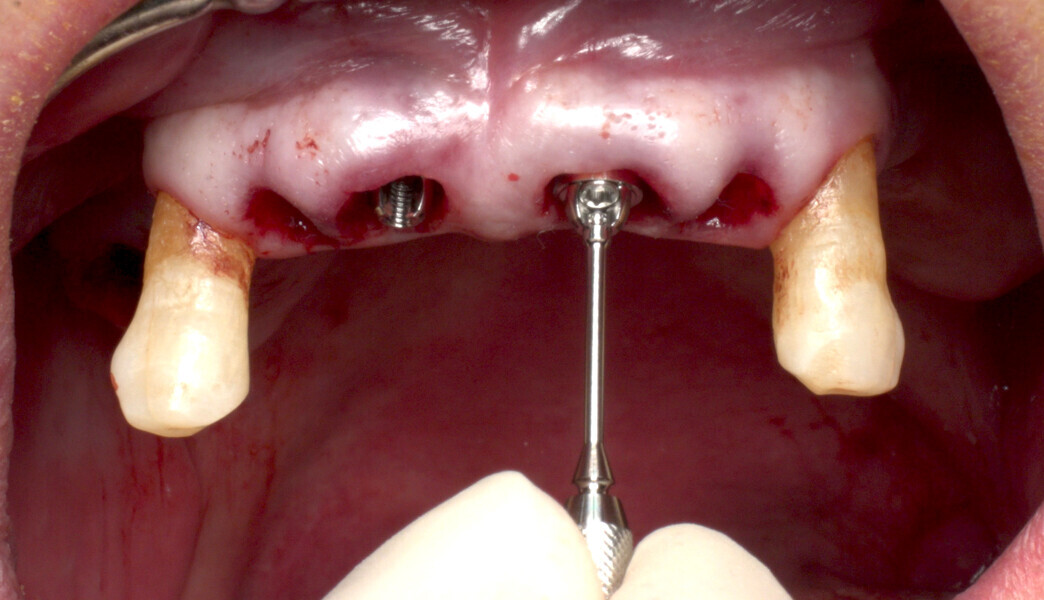

The fully digital Pro Arch protocol